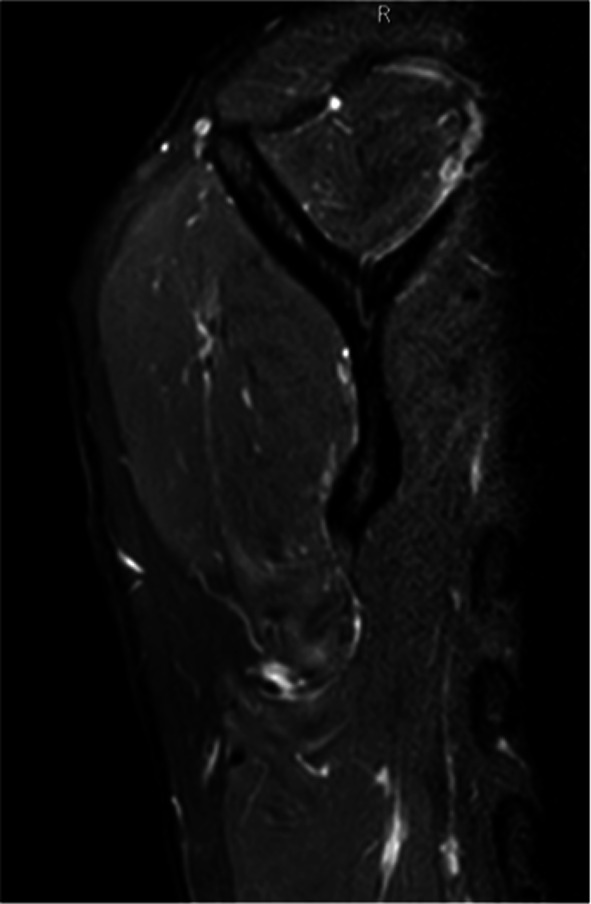

Background: Quadrilateral space syndrome is a painful disorder of the shoulder caused by static or dynamic entrapment of the axillary nerve and the posterior humeral circumflex artery. It was first described in 1983; however, it is an uncommon syndrome that initially presents with nonspecific shoulder pain or selective deltoid atrophy, and diagnosis is often delayed owing to its rarity. Young athletes of overhead sports are more commonly affected by this syndrome. Symptoms of quadrilateral space syndrome include silent deltoid atrophy, persistent posterior shoulder pain, paresthesias, and tenderness over the quadrilateral space. Vascular symptoms may involve thrombosis and embolisms of the upper limb. Instrumental tests and imaging are not always conclusive, leading to frequent misdiagnosis of the syndrome.

Patients and methods: The aim of this study is to present a case series of four patients diagnosed with neurogenic quadrilateral space syndrome, describe different clinical presentations, and suggest tips for diagnosing this syndrome. All patients underwent a detailed medical history collection, were interviewed about the sports and hobbies they engaged in, and received a comprehensive clinical examination of the neck and shoulder. Patients also underwent diagnostic exams such as magnetic resonance imaging (MRI) and electromyography. An ultrasound-guided injection of local anesthetic was performed into the quadrilateral space.

Conclusions: To properly treat this rare syndrome, we propose classifying it as either "dynamic" or "static," on the basis of the clinical history, MRI findings, and physical examination. The study includes a rehabilitation program that was effective for one patient, demonstrating that surgical decompression may be avoidable if the cases are promptly diagnosed and classified. Level of evidence IV according to "The Oxford 2011 Levels of Evidence".